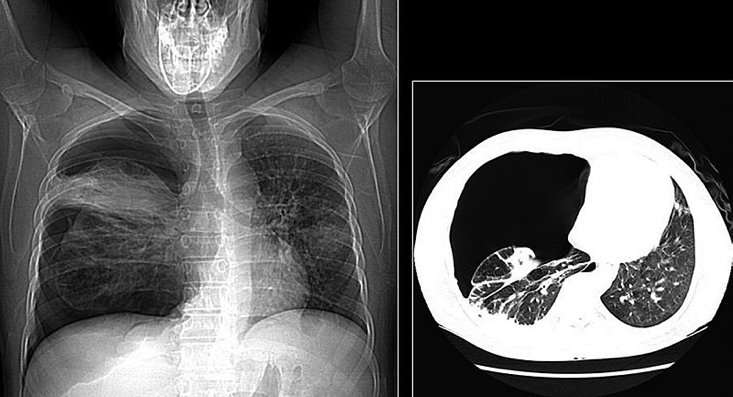

- Chest X-ray:

- Absent peripheral lung markings

- Visible pleural line

- Collapsed lung margin

- Mediastinal shift (in tension pneumothorax)

- CT Chest:

- Better sensitivity for small pneumothoraces or when looking for cause (e.g. tumour, rib fracture)